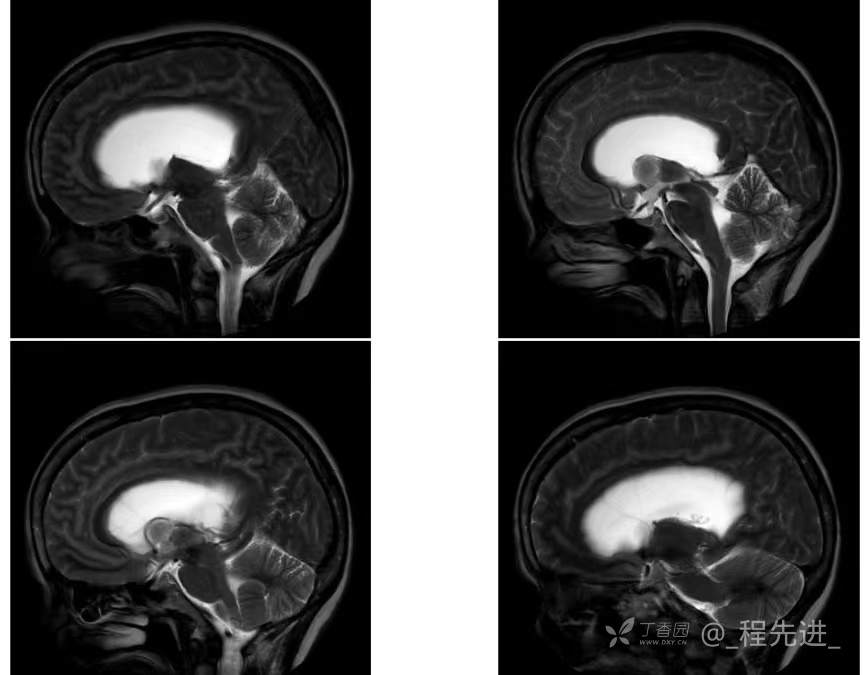

患者性别:女

患者年龄:55岁

简要病史:头痛头晕4年余,无明显诱因,10余年前因“输卵管破裂大出血”手术治疗

脑膜瘤 (78)

过渡型(混合性)脑膜瘤 (1)